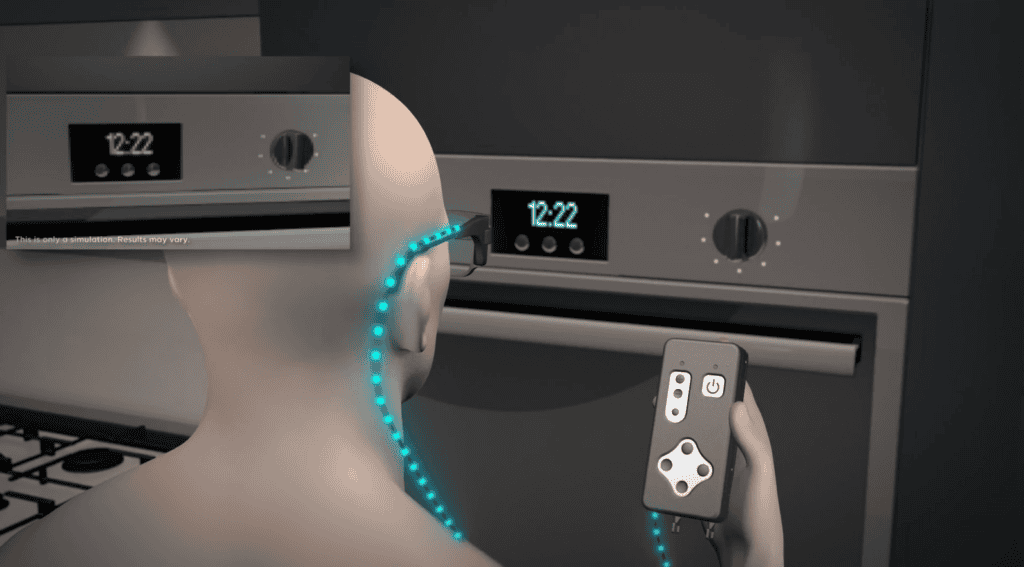

ชิป Prima ประกอบด้วยชิปสี่เหลี่ยมจัตุรัสขนาด 2 มม. ที่ถูกผ่าตัดวางไว้ใต้จอประสาทตา ตรงส่วนหลังสุดของลูกตา โดยใช้เวลาผ่าตัดนานถึง 80 นาที โดยจะใช้งานร่วมกับแว่นตาพร้อมกับกล้องที่จะบันทึกภาพ และส่งแสงอินฟราเรดไปยังชิป แล้วชิปดังกล่าวจะทำหน้าที่เสมือนแผงโซลาร์เซลล์ขนาดเล็ก ที่จะแปลงแสงเป็นการกระตุ้นไฟฟ้า และส่งไปยังสมอง จากนั้นสมองจะตีความสัญญาณดังกล่าวเป็นภาพ ซึ่งเป็นการเลียนแบบกระบวนการการมองเห็นตามธรรมชาติ